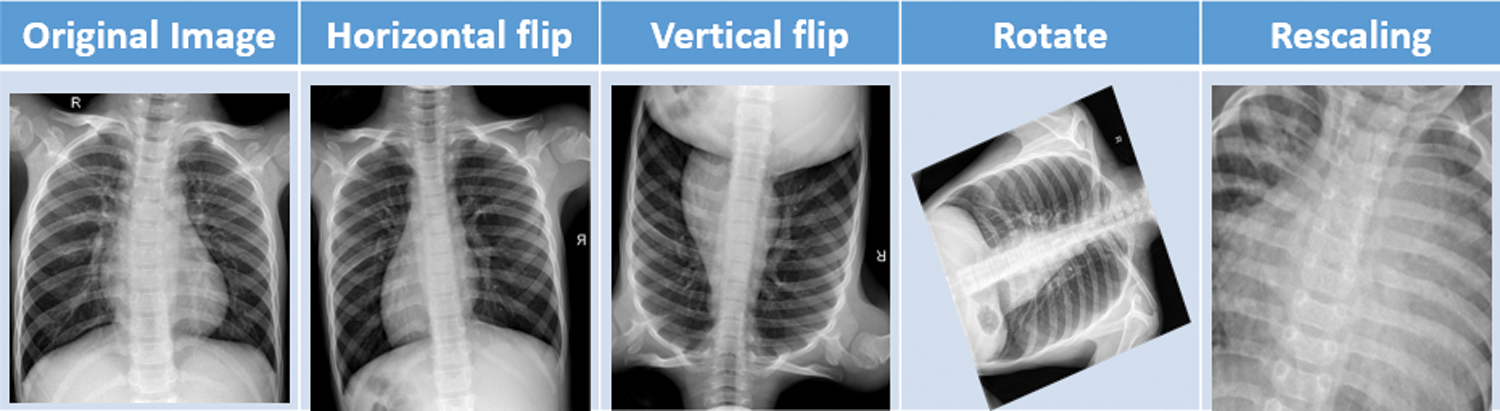

After obtaining the dataset [14] from kaggle, we applied some preprocessing task on it. Image data augmentation is a technique, that we have used in our article to artificially increase the size of our training dataset by creating modified versions of images in the dataset. Image data augmentation is used to increase the size of the training dataset in order to improve the performance and capability of the models used in this article. Data augmentation techniques such as padding, cropping, rotating, resizing and flipping are the most common methods that are we used over the images to increase the size of the dataset. In this project we have done data augmentation through some parameters or measurements which is mentioned in Tab. 4. Fig. 3 shows the different data augmentation techniques that we applied on the dataset.

Figure 3: Sample data augmentation